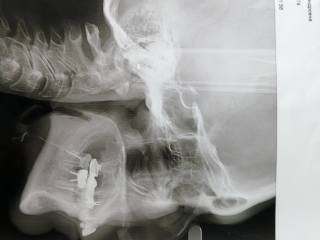

Я мечтаю о ортогнатической операции

19 лет я получила травму-перелом верхней и нижней челюсти со смещением, были в травмпунке наложены шины на месяц и отправили домой, на сустав никто